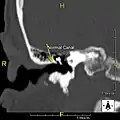

Surfer's ear is the common name for an exostosis or abnormal bone growth within the ear canal. They are otherwise benign hyperplasias (growths) of the tympanic bone thought to be caused by frequent cold-water exposure.[1] Cases are often asymptomatic.[1] Surfer's ear is not the same as swimmer's ear, although infection can result as a side effect.

Irritation from cold wind and water exposure causes the bone surrounding the ear canal to develop lumps of new bony growth which constrict the ear canal. Where the ear canal is actually blocked by this condition, water and wax can become trapped and give rise to infection. The condition is so named due to its high prevalence among cold water surfers, although it can occur in any water temperature due to the evaporative cooling caused by wind and the presence of water in the ear canal.

The normal ear canal is approximately 7 mm in diameter and has a volume of approximately 0.8 ml (approximately one-sixth of a teaspoon).[5] As the condition progresses, the diameter narrows and can even close completely if untreated, although people generally seek help once the passage has constricted to 0.5–2 mm due to the noticeable hearing impairment. While not necessarily harmful in and of itself, constriction of the ear canal from these growths can trap debris, leading to painful and difficult to treat infections.